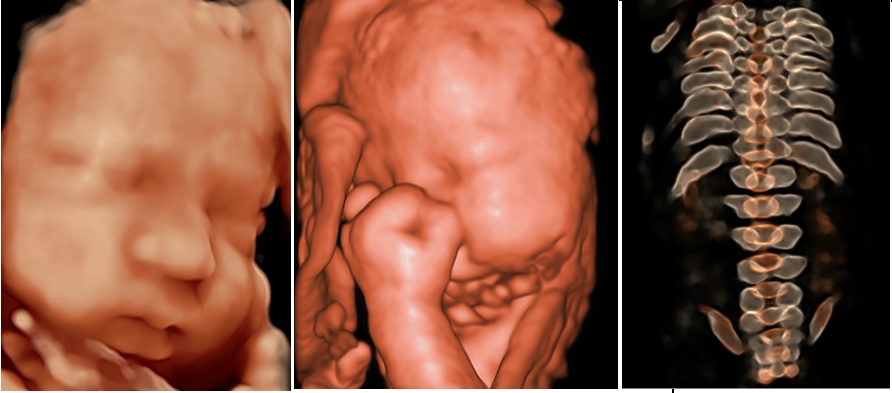

S FETUS

S-Fetüs Obstetrik Ultrason İş Akışını Otomatikleştirir S-Fetus, standart obstetrik ultrason prosedürünü basitleştiren bir fonksiyondur. %80 daha az tuş vuruşu %90 daha az zaman %95'ten fazla doğruluk